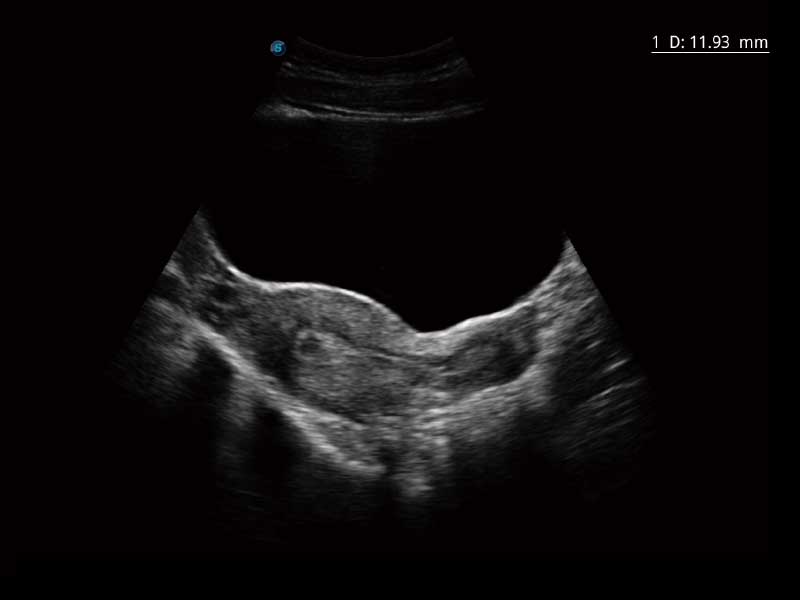

E2便携式彩色多普勒超声诊断系统采用专业的超声技术平台、高度集成化的硬件模块和结构设计、简便的操作流程、多探头接口设计,兼顾了优质图像、轻便机身以及台便两用的临床使用需求。

μ-Scan微米成像、空间复合成像、高分辨率血流成像。

单键操作,可快速优化多个二维及多普勒图像参数,获得优异图像效果。